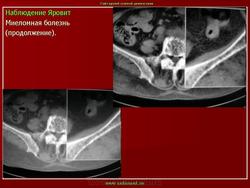

продолжение.

Миеломная болезнь